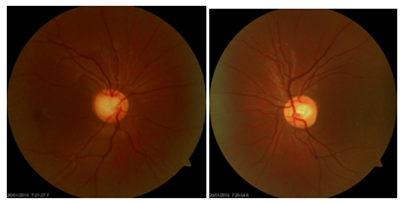

Vitreous revealed multiple bands like opacities. Fundus examination revealed a cup disc ratio of 0.7, with inferior thinning of the neuroretinal rim in the right eye and a cup disc ratio of 0.6, with inferior thinning of the neuroretinal rim in the left eye (Figure 2). Periphery of the retina showed lattice degeneration superiorly in both eyes (Figure 3A). Intraocular pressures were 25 mm Hg in the right and 17 mm Hg in the left eye respectively on two consecutive occasions. Gonioscopy revealed open angles with a 3+ trabecular pigmentation in both eyes (Figure 3B). Humphrey’s visual field (24-2) both eyes were within normal limits. Optical Coherence Tomograph (OCT) both eyes revealed an overall reduction of the nerve fibre layer when compared to the OCT reports of age matched patients in various studies. Central corneal thickness was 538 microns in the right eye and 542 microns in the left eye which was within normal limits.

Figure 2 Disc photos of right eye and left eye: Arrows showing thinning of neuroretinal rim in both eyes respectively.